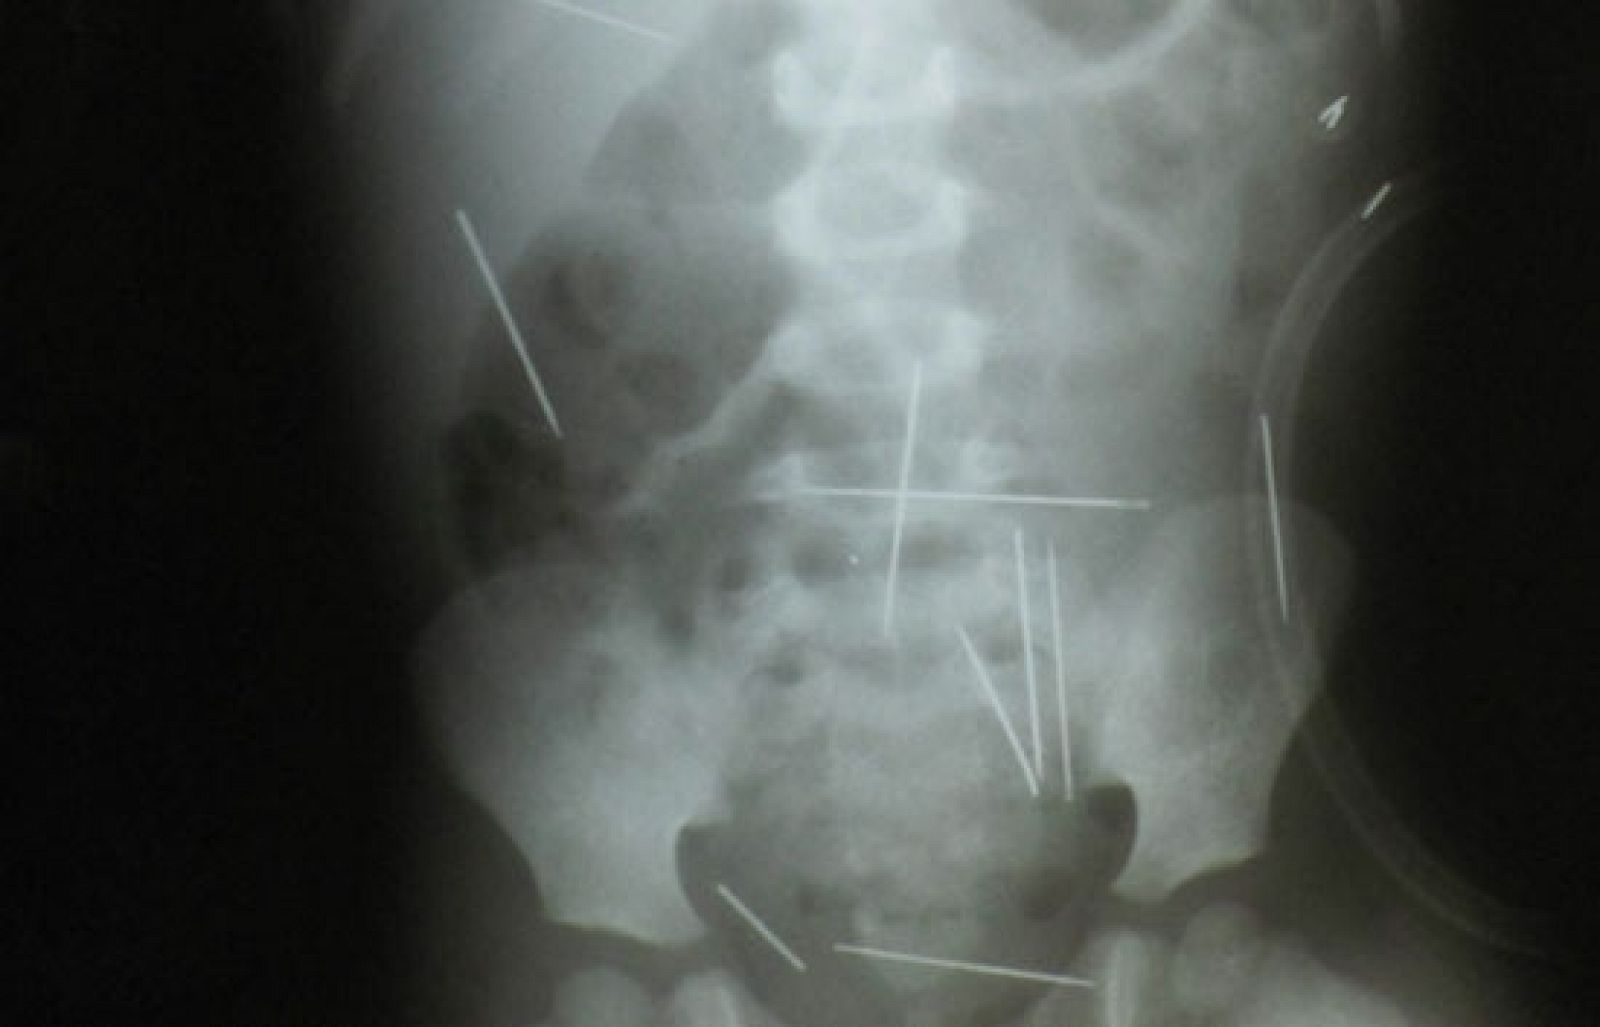

El médico que lo trata ha dicho que intentará sacárselas pero que es difícil porque algunas están demasiado cerca de órganos vitales.